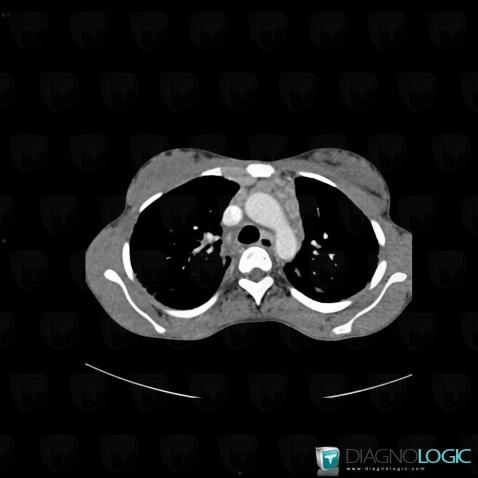

Sarcoïdose, Médiastin, Scanner

Voici les informations spécifiques à l'image clé ci dessus:

- Diagnostic Sarcoïdose, Localisation(s) Médiastin, comportant les gammes Masse médiastinale moyenne